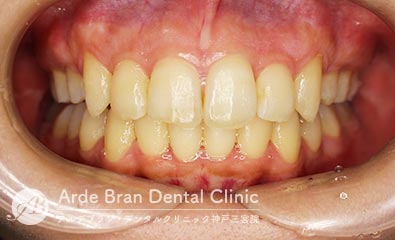

- 上顎前突(出っ歯)/叢生

(20代女性 治療期間2年5カ月) - 前歯の突出感と歯のがたつきを改善したいとの事でご来院されました。なるべく目立たない装置で治療をしたいとご希望されたのでマウスピース矯正にて治療を行いました。治療途中に治療計画とのズレが生じましたが、顎間ゴムを使用しリカバリーを行いワイヤーで修正をかける事なくフィニッシュ出来ました。ワイヤーを併用だともう少し治療期間は短縮出来たかと思います。口元の突出感が改善し、歯磨きもしやすくなったとお喜び頂きました。

- 治療前

- 治療後

| 装置名 | インビザライン (マウスピース矯正) |

|---|---|

| 抜歯非抜歯 | 上顎第一小臼歯の抜歯(合計4本) |

| 治療期間 | 2年5カ月 |

| 費用 | インビザラインフル(難症例) 79万円+TAX 抜歯(5千円+TAX)×4本 再印象(5千円+TAX)×2回 顎間ゴム500円×数個 |

| リスク副作用 | 装置装着による違和感、歯の移動時の痛み、歯根吸収など。詳しくはこちらをご参照ください。 |